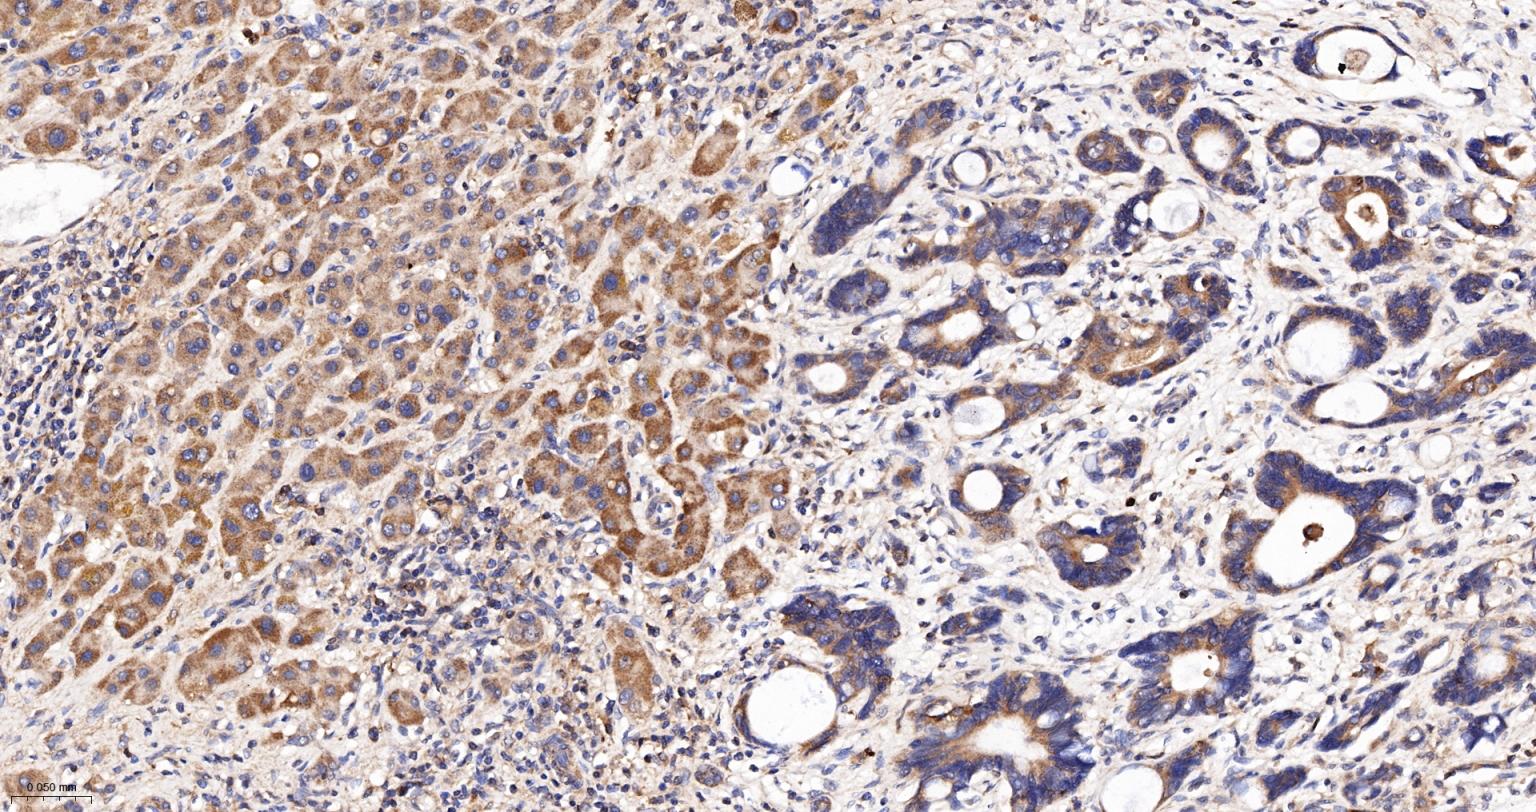

Paraformaldehyde-fixed, paraffin embedded Human Gastric Cancer; Antigen retrieval by boiling in sodium citrate buffer (pH6.0) for 15 min; Antibody incubation Glucose 6 Phosphate Dehydrogenase Monoclonal Antibody, Unconjugated(bsm-61479R) at 1:200 overnight at 4°C, followed by conjugation to the bs-0295G-HRP and DAB (C-0010) staining.